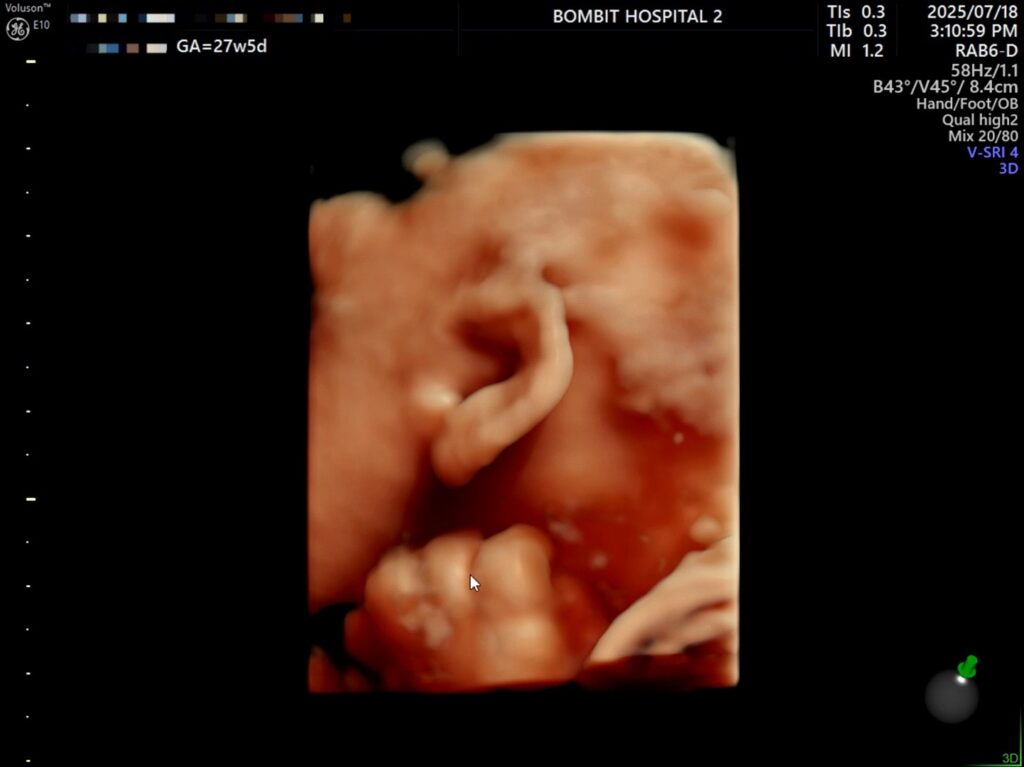

– 처음에 보여준 귀.. 귀욥